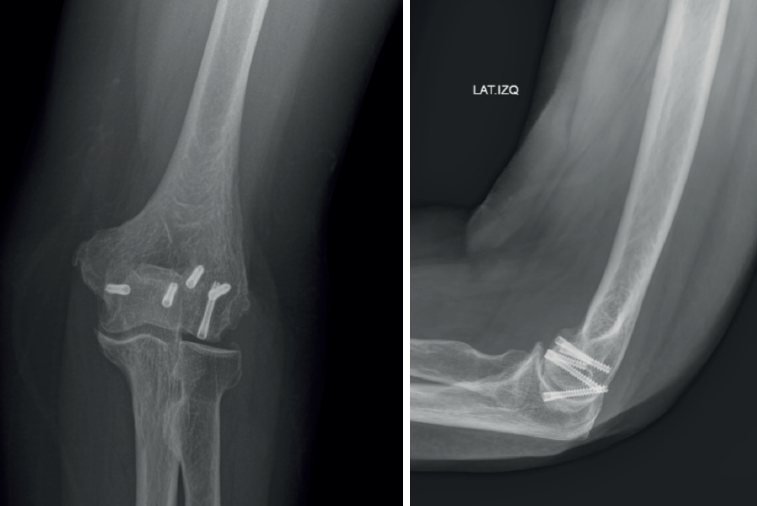

Es el método de fijación más comúnmente utilizado en las fracturas coronales del codo, consiguiendo buenos resultados publicados(1,7,26,27,28,29,30,31). En cuanto al sentido en la introducción del tornillo y el tipo, los estudios(32,33) nos orientan a la utilización de tornillos de 4 mm de rosca completa introducidos en sentido anteroposterior porque reduce la necesidad de realizar una disección posterior en el capitellum y, por tanto, no reduce el aporte sanguíneo. El uso aislado de tornillos como método de osteosíntesis en estas fracturas estaría indicado en las de tipo 1A, 2A y 3A porque la conminución posterior no permitiría conseguir una fijación estable(1,7,28,29,30).

Las placas posterolaterales se deben utilizar para aquellas fracturas de tipo 1B, 2B, 3B y 4, es decir, aquellas fracturas que presenten conminución posterior, para originar una cortical posterior sobre la que poner los tornillos que sintetizan la fractura en sentido posteroanterior. Además, las placas laterales tienen también su papel cuando existe asociada una fractura del epicóndilo, permitiendo su fijación y la fijación suplementaria de la tróclea.